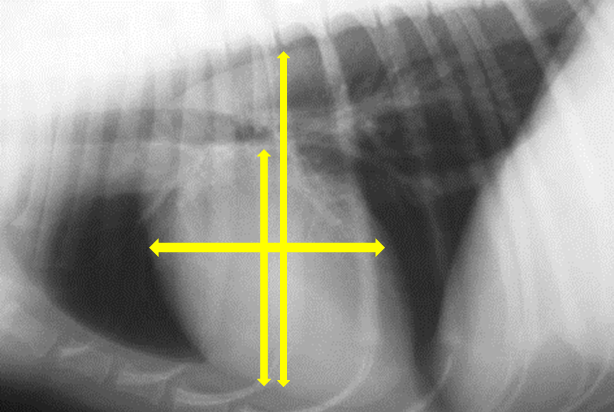

What is the vertebral heart score?

Add the no. of vertebrae

Suggested normal range

= 8.5 – 10.5

Breed specific values available

•Normal ranges differ between breed so always refer to this